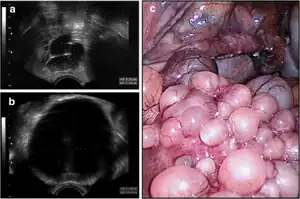

| Paratubal cysts | ||

| Tubo-ovarian abscess |